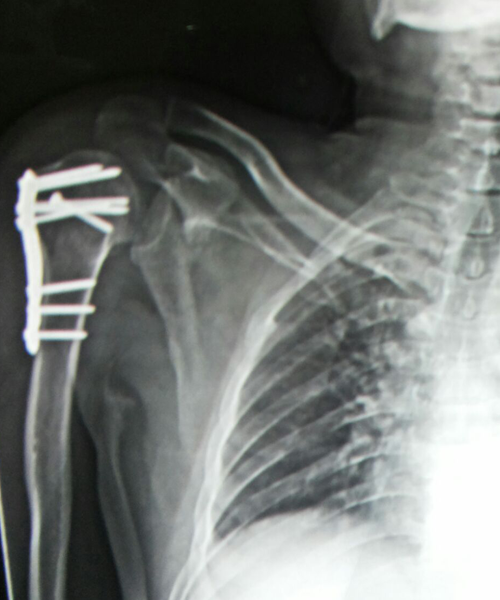

Case:2 Fracture of Neck Humerus with Fracture of Greater Tuberosity

Pre-Op AP

Pre-Op Trausaxillay

Post-Op X-ray